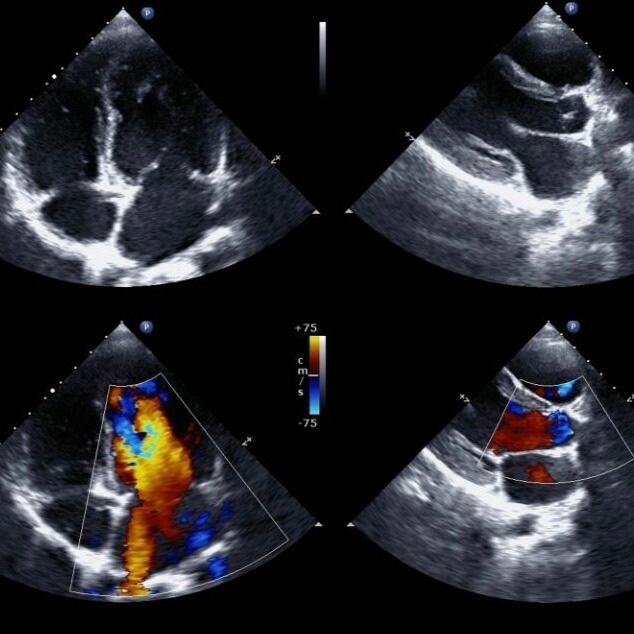

Ultraschalluntersuchungen